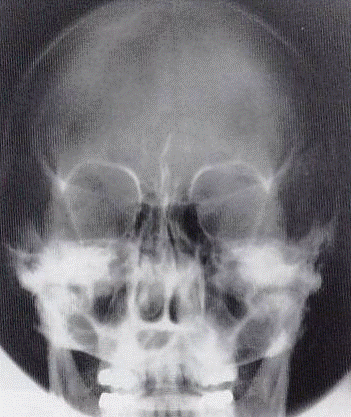

Patología Demostrada

Fracturas y alteraciones de los huesos faciales:

Estructuras Anatómicas Visibles

Órbitas simétricas, senos frontales nítidos, sin rotación.

Caldwell vs Waters

CALDWELL

Angulación: 15° caudal

Punto salida: Nasión

Mejor visualiza: Senos frontales, órbitas